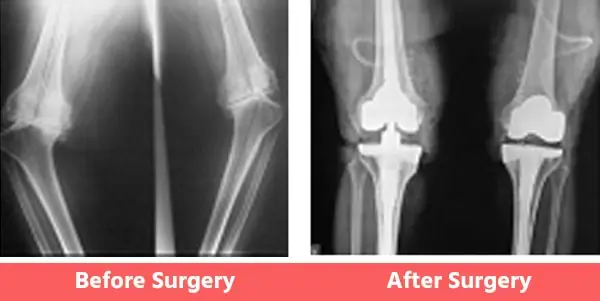

People may have certain deformities of the knee which include bow legs (varus), knock knees (valgus), or even wind-swept legs.

In such cases, the surgeon has to be well-experienced in handling such cases and should also have had considerable experience with revision joint replacement surgeries as well. See below Images.

1. Bow Legs (Varus Knee)

2. Knock Knees (Valgus)

3. Wind Swept Legs

Some Common Deformities

1. Bow legs (Varus)

You can see illustration and X-Ray images shown above already.